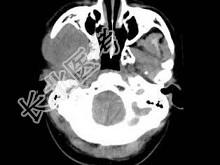

- 单项选择题男,30岁, 感右下颌部有一肿物,逐渐肿大, 胀痛,局部麻木1月余, 结合图像,最可能的诊断是 ( )

A、神经纤维瘤

B、神经鞘瘤

C、血管瘤

D、下颌骨肉瘤

E、软骨瘤